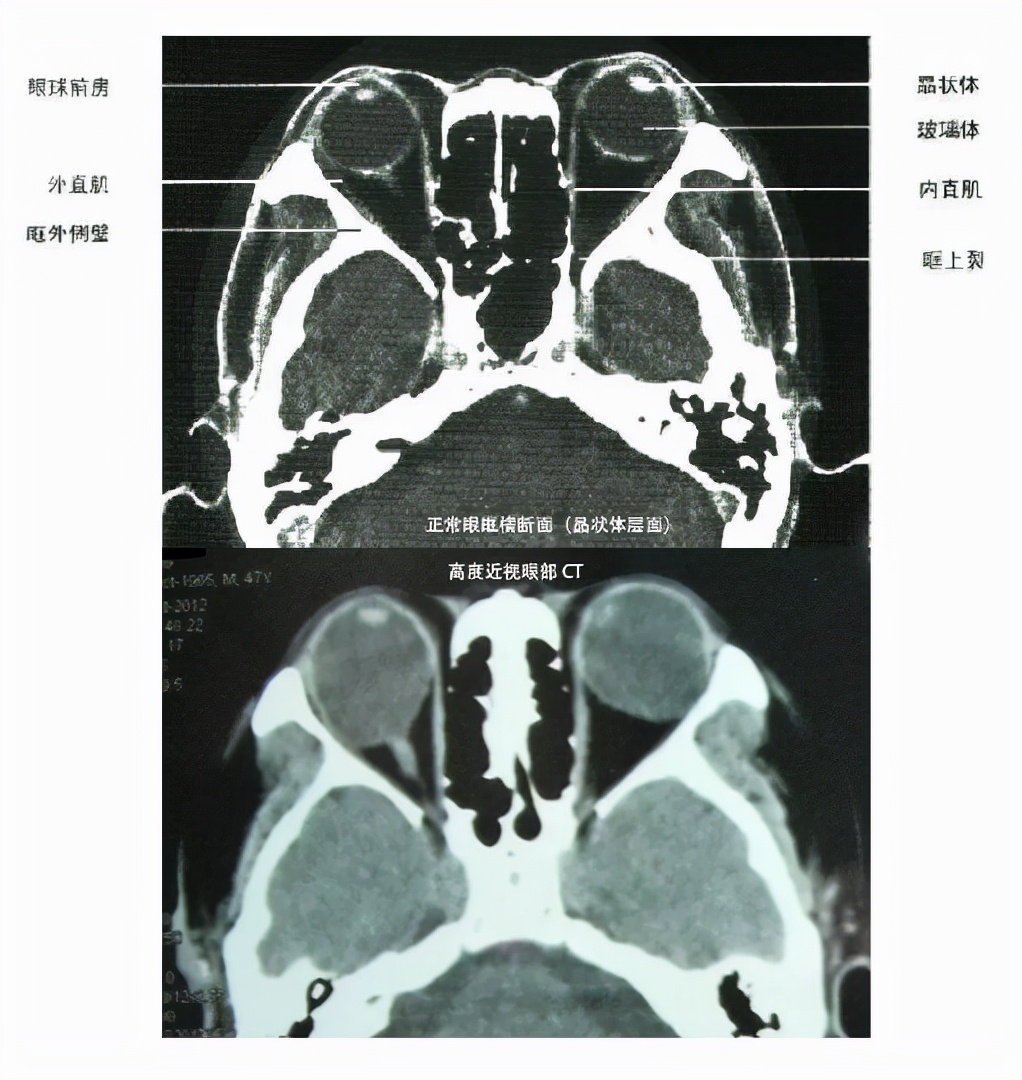

正常眼眶横断面(晶状体层面)与高度近视眼部CT对比

正常的眼睛的眼轴长度在23.5-24mm。

近视眼的眼轴长度会大于这个正常值,眼轴每增加1mm,近视度数增长300度左右。